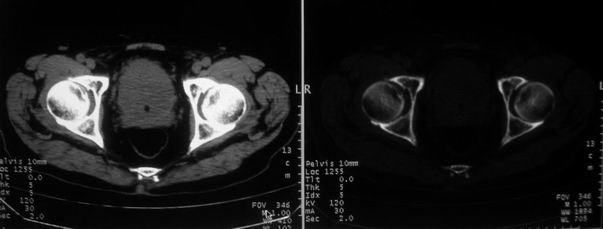

男,85岁,排尿困难。骶椎有问题吗?

前列腺明显增大,突入膀胱,各叶比例协调,密度均匀,精囊腺及精囊角正常;考虑良性增大。

这个病人排尿困难应该是前列腺增生造成的,ct对前列腺增生及前列腺癌诊断有一定限度,只能判断前列腺增大,建议还是做一个mr来鉴别一下增生或癌更好,因为增生多发生于中央带,癌多发生于周围带,而mr t2加权图像上中央带和周围带的信号有区别,因此诊断价值更高一些。

前列腺增生明显,肿瘤待排,建议mri 检查

1)前列腺明显增大,突入膀胱,各叶比例协调,密度均匀,精囊腺及精囊角正常;考虑前列腺增生症并阻塞性膀胱炎。2)骶椎右侧类似囊状骨质密度减低区,边缘骨质硬化,其内为软组织密度影填塞,相邻之骶椎椎管受压变形;考虑为骶椎右侧囊肿或神经纤维瘤。

建议:行mri检查。